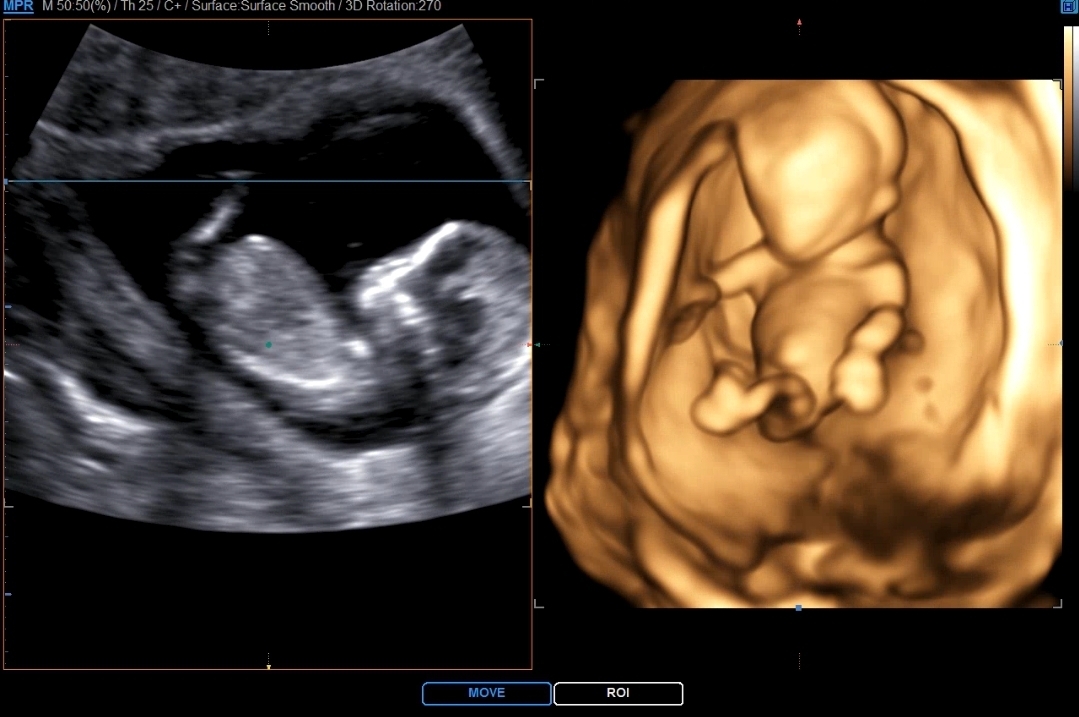

각도법 성별예측 부탁드려요!

12주차입니당! 각도법 고수님들 성별예측 부탁드려요ㅎㅎ